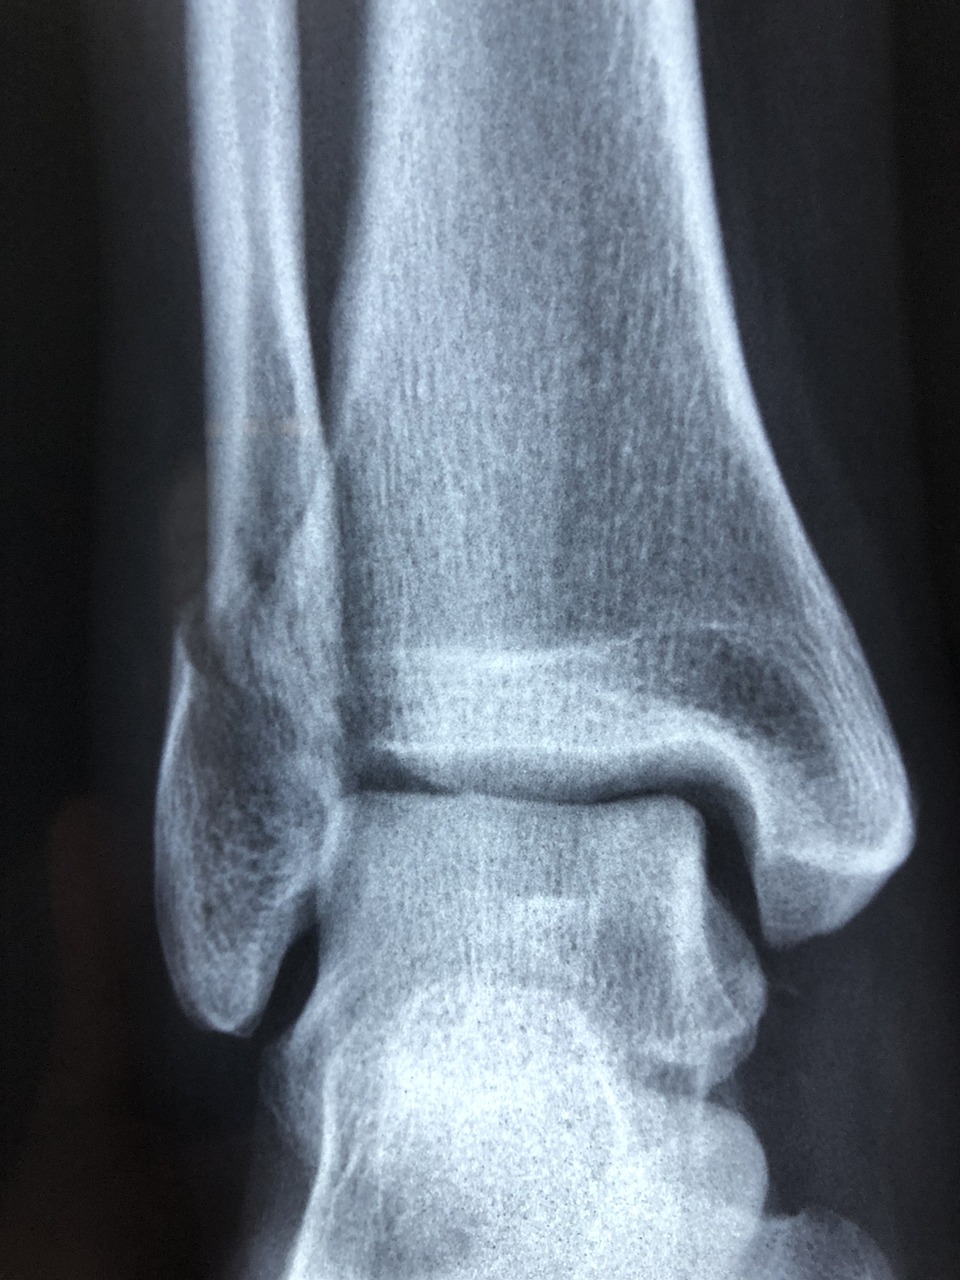

Le centre est équipé d’une radiologie standard, permettant le diagnostic rapide des traumatismes et des pathologies ostéo-articulaires. Les échographies diagnostiques sont assurées sur rendez-vous par le Dr Yannick Lebreton, du Centre Radiologique de la Glâne, garantissant un accès direct à l’imagerie de haute qualité.